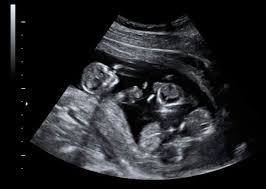

A fin de mes, está programado en el Hospital de Alta Complejidad María Humphreys de Trelew el parto de las primeras trigemelas de la ciudad, un caso que se presenta en uno de cada un millón de embarazos.

Las tres bebés, que se desarrollan a partir de un único óvulo fecundado que se dividió en tres embriones.

El último caso similar registrado en Argentina ocurrió este año en Salta, donde nacieron tres niñas a las 34 semanas de gestación.